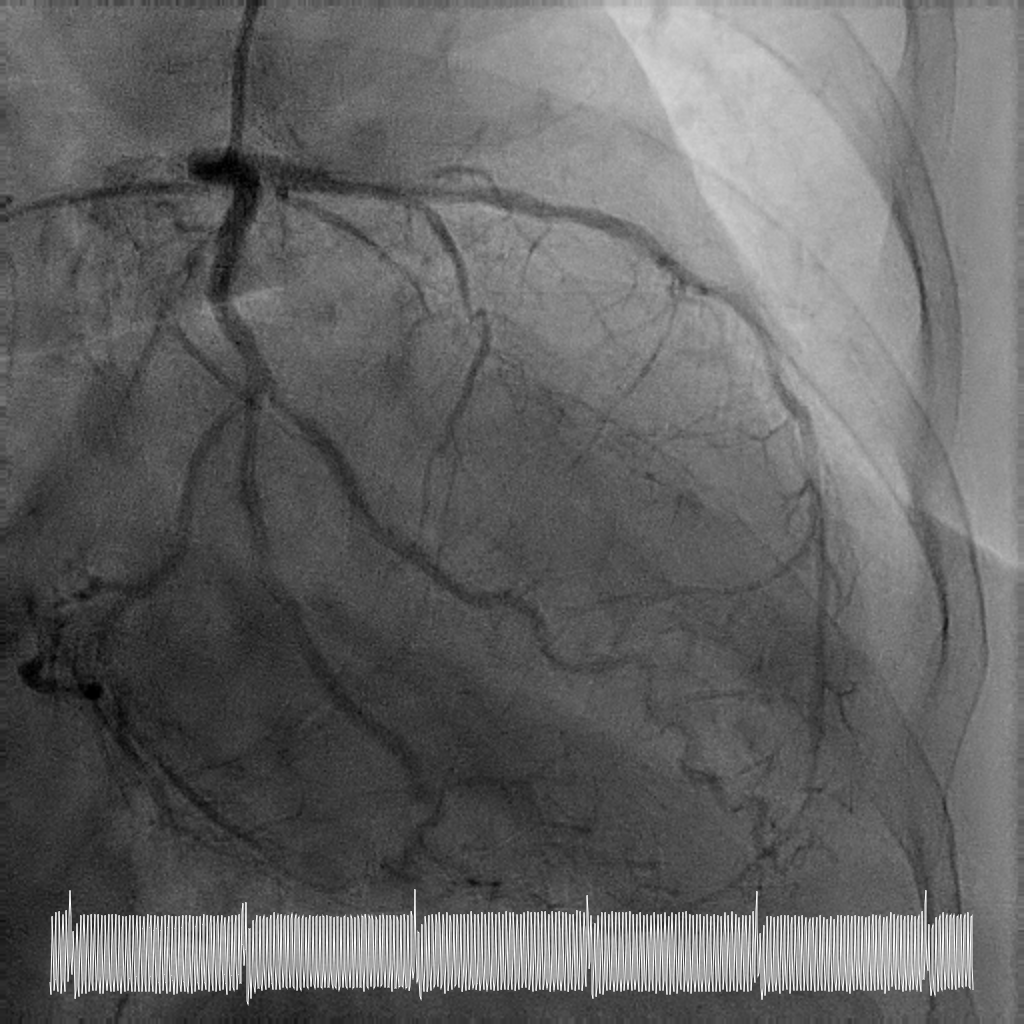

Rotational atherectomy with 1.5mm and then 2mm was performedfrom ostial LM to proximal LCx. Wiring of the LAD was only successful till midLAD with a separate distal LAD occlusion. LAD lesion was balloon uncrossableand half-way rotational atherectomy with 1.5mm burr. The distal LAD CTO wasthen crossed and balloon angioplasty undertaken. There was diffuse LAD disease, and the plan was then for ahybrid strategy. PCI to LM bifurcation was secured using the DK crushtechnique. 3.5x23mm Xience Sierra was placed in the LCx, 3.5x16mm Megatron inLM to proximal LAD followed by drug coated balloon angioplasty for the rest ofthe LAD with 2x40mm, 2.5x40mm, and 3x25mm balloon. She recovered well after her intervention and is infunctional New York Heart Association Class I, Canadian Cardiovascular Society Angina Grade 0. An elective angiogram was performed 6 months after indexprocedure to re-assess the results. This showed widely patient stents acrossthe LM-LAD-LCX, and excellent DCB results across the proximal to distal LAD andimprovement of her left ventricular ejection fraction.

This case illustrates the feasibility of a hybridrevascularisation strategy combining two-burr rotational atherectomy, left mainbifurcation stenting with DK crush, and downstream drug-coated balloonangioplasty in a patient with prohibitive surgical risk. Careful lesionpreparation and strategic device selection resulted in sustained long-termvessel patency and recovery of ventricular function in a patient with extreme-riskanatomy.